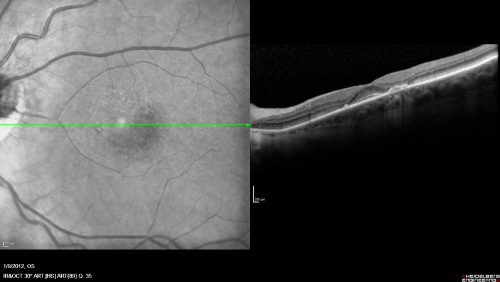

Plaquenil Toxicity both Eyes - Partial Bull's Eye - Discontinued 6 Years ago SD-OCT (Spectral domain optical coherence tomography)

82-year-old woman was on Plaquenil from 1976 from 2005, 200 mg a day.  It was discontinued because of abnormal visual fields 6 years ago. OD 20/32,  OS 20/40